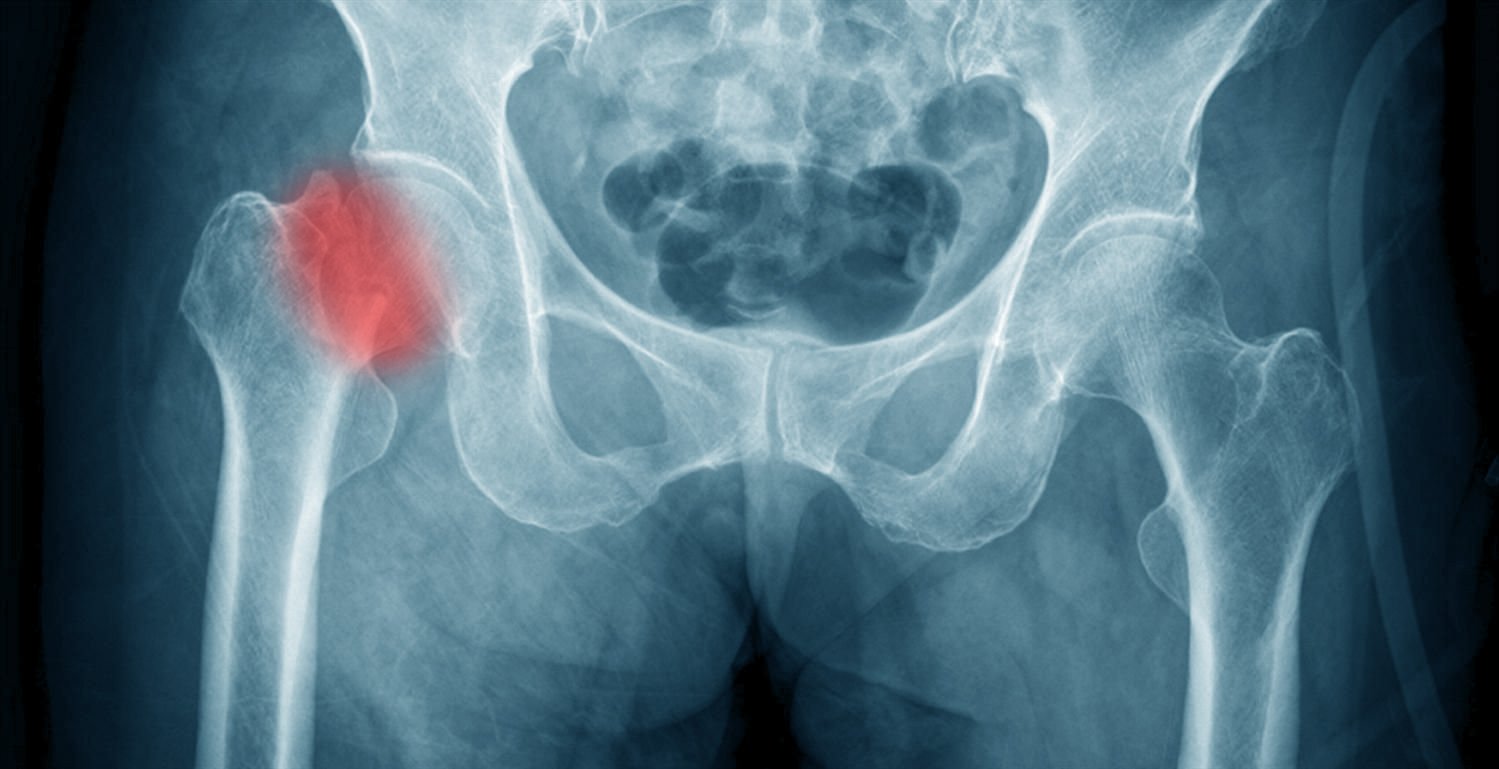

أنواع كسور أعلى عظمة الفخذ

يمكن أن تحدث كسور الورك في عدة مناطق من الجزء العلوي من عظم الفخذ، وأكثر أنواع كسور الورك شيوعًا هي:

- كسور رأس عظمة الفخذ (fracture femoral head) و هى كسور نادرة غالبا تصاحب خلع مفصل الفخذ و لن نتناولها فى هذه الصفحة

- كسر عنق عظمة الفخذ (fracture neck femur): هي منطقة العظم أسفل رأس الفخذ (الكرة).

- كسر أسفل عنق عظمة الفخذ (كسر بين المدورين Trochanteric fracture ): وهي كسر جزء من عظم الفخذ يقع بين عنق الفخذ والجزء الطويل المستقيم من عظم الفخذ.

تشخيص كسور الفخذ(الورك)

لتشخيص الكسر والتحقق من تلف الأنسجة الرخوة قد يطلب الطبيب بعض الأشعات:

- الأشعة السينية: والتي تستخدم الإشعاع لإنتاج صور لمفصل الفخذ لتحديد مكان الكسر بدقة و للتأكد من عدم وجود أي إصابات أخرى و عادة تكون هذه الاشعة كافية للتشخيص.